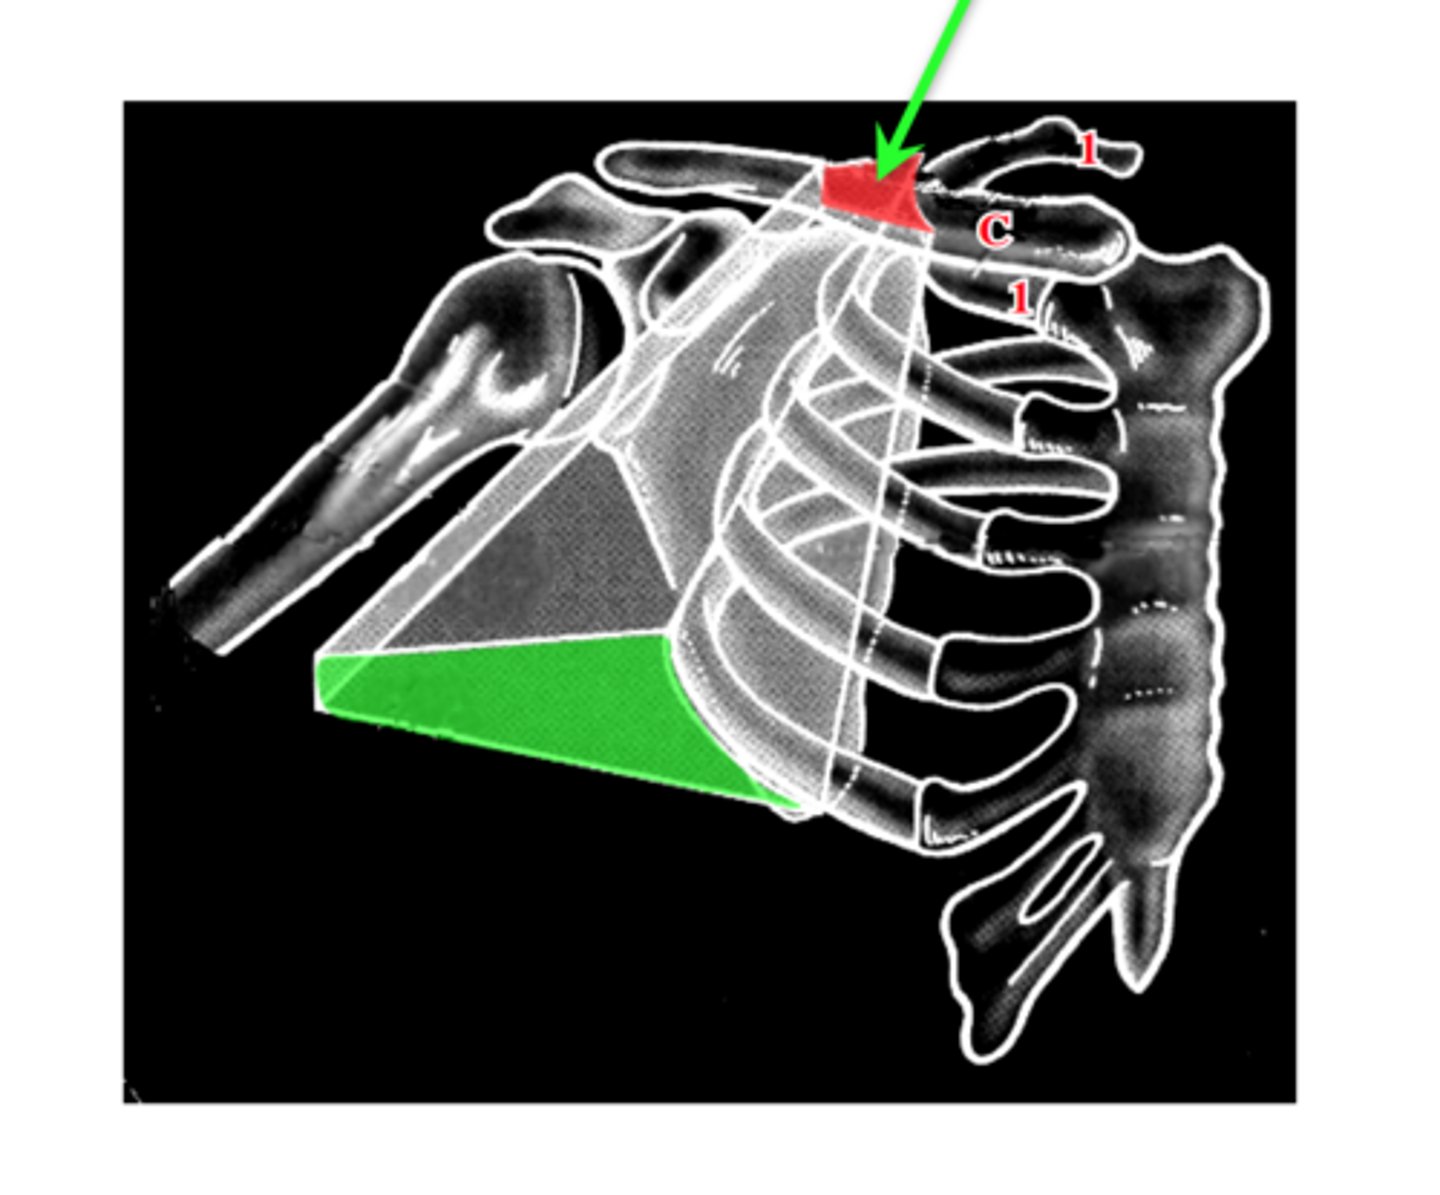

one of the boundaries of the cervico-axillary canal together with the scapula and 1st rib

What is the cervico-axillary canal?

passage between neck and arm

What does the cervico-axillary canal do?

protects the neurovascular bundle supplying the arm